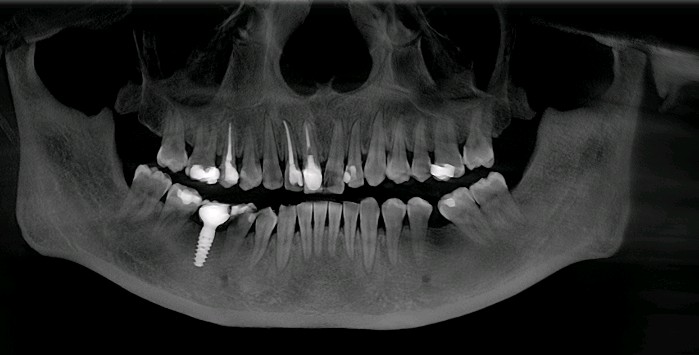

患者女,三十岁,12,11已行根管治疗,未做修复。牙齿发生了变色。其原因是牙齿出现神经炎症或坏死,经过根管治疗后,牙齿会失去来自牙髓的营养供应。这就好比一棵树一旦失去了根系,就会逐渐枯萎一样,慢慢的色泽也会发生变化。死髓的牙齿由于缺乏活力,会逐渐变色,甚至变黑,影响美观。21,23近中龋坏可行全瓷贴面,减少基牙的磨出面积的同时又能更好的恢复牙齿的自然色泽,使牙齿看起来更加健康和美观。

术前

术中

术后